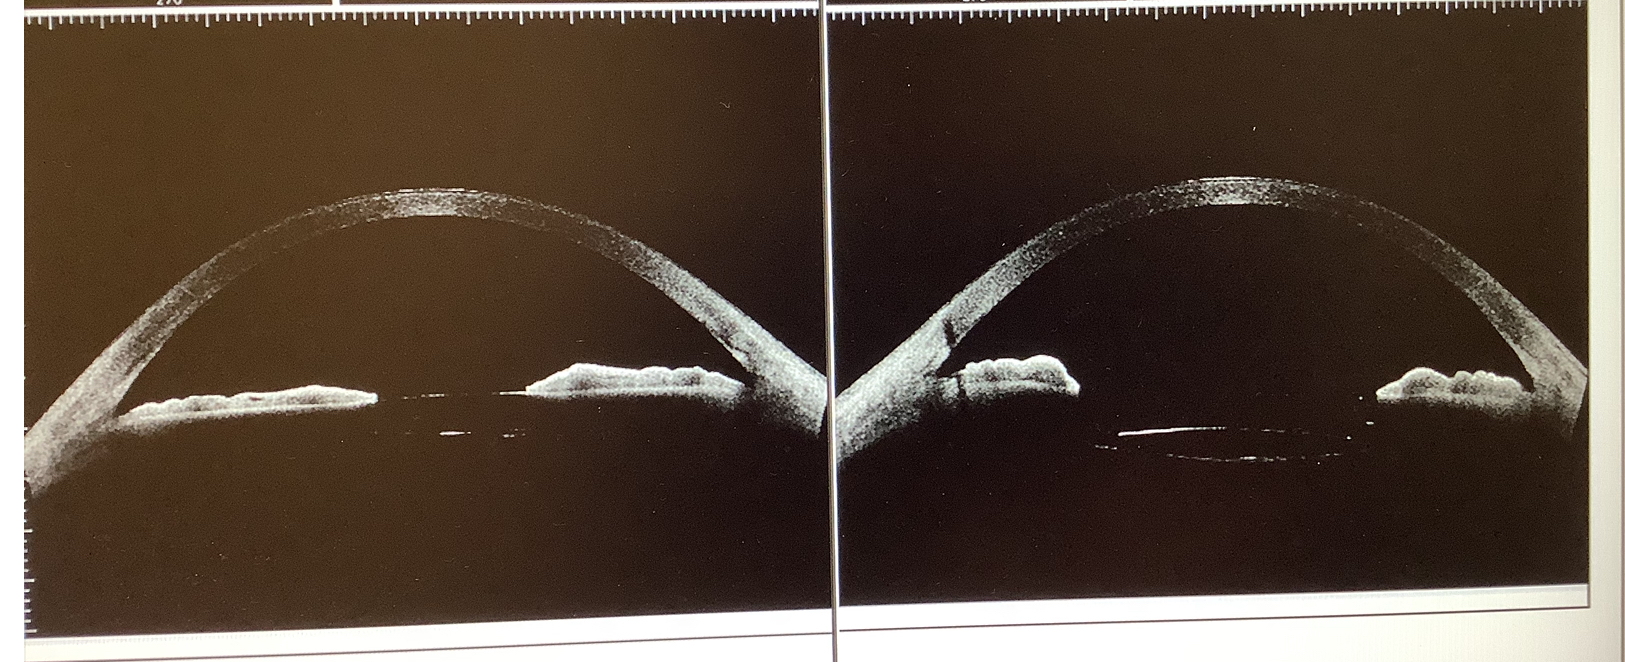

今日の手術では、眼内レンズを嚢内固定から嚢外固定に変える手術を行いました。なぜ、こんなことをしたかというと、この患者さんは元々、昨年の8月に他院で両眼の白内障の手術を受け、左眼は通常の予定通り、水晶体の袋(水晶体嚢)の中にレンズ(アイハンス)を入れて(嚢内固定)終えたものの、右眼は水晶体嚢の後面(後嚢)が破れてしまい(後嚢破損)、脱出する硝子体(硝子体脱出)の処理を行ったのちに、3ピースタイプのレンズを水晶体嚢の上に入れて(嚢外固定)終えたそうです。それで、うまくいった方の眼である左眼が『術後から、曇った感じが気になる』と当院を受診されました。

左右の眼の違いとしては、レンズの種類が違う、レンズの入っている位置が違う、前の方の硝子体(前部硝子体)の処理をしているかの3つがありました。その中で一番可能性が高いかと思われ、十分、症状の原因になりうると思われたのが、レンズの種類の違いだったので、5月にアイハンスから右と同じ単純な単焦点の3ピースレンズへ入れ換えました。多少は症状が改善したものの、やはり症状が続くということで、少しでも左右の違いを無くしてみるという意味で、今回、嚢内に入れた眼内レンズを嚢外に固定し直しました。嚢外固定することで、レンズと虹彩の距離が変わると、眼の中への光の入り方が多少変わるので、もしかすると症状が改善してくれるかなと淡い期待を持ちながら、もしこれでも変わらないなら、あとあるとすれば、硝子体の影響かと思うので、もし残念ながら今回の処置で改善が得られず、更に何かしらの治療を患者さんが望まれるなら、硝子体の切除を考えたいと思います。